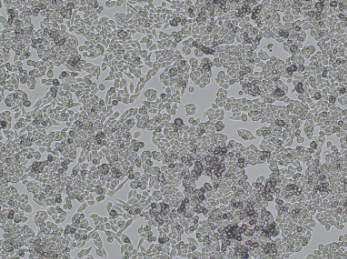

SUIT-2 is a human pancreatic cancer cell line derived from a liver metastasis of moderately differentiated tubular adenocarcinoma in a Japanese male patient. The cells exhibit an epithelial-like morphology with two distinct subpopulations under phase-contrast microscopy: one spindle-shaped and elongated, the other polygonal and epithelial. SUIT-2 cells express several pancreatic ductal markers including carcinoembryonic antigen (CEA), carbohydrate antigen 19-9 (CA19-9), CSPG2/versican, and Mac25/angiomodulin. Electron microscopy confirms features of pancreatic ductal epithelium. Karyotype analysis shows aneuploidy, consistent with malignant transformation. SUIT-2 cells are tumorigenic and metastatic, capable of forming tumors and spreading to regional lymph nodes in nude mouse xenografts.